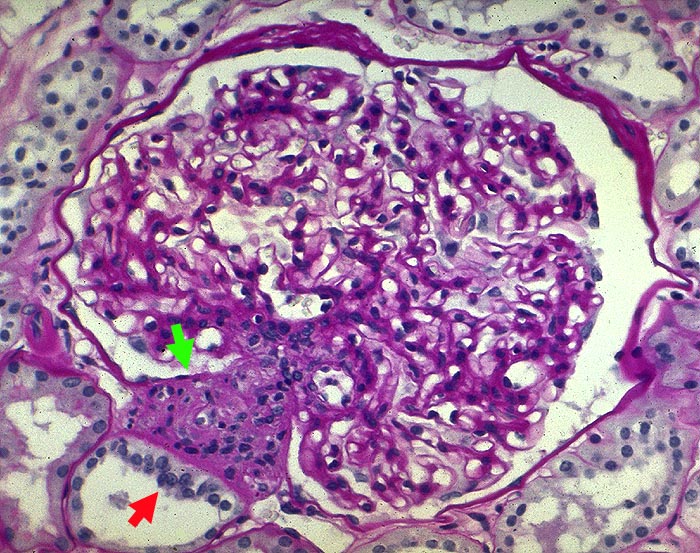

PathoPic ID 1604 - Juxtaglomerulärer Apparat mit Macula densa

Juxtaglomerulärer Apparat mit Macula densa

Normalbefund

Niere

Normaler Glomerulus.

Juxtaglomerulärer Apparat mit

Macula densa. Zartes Mesangium.